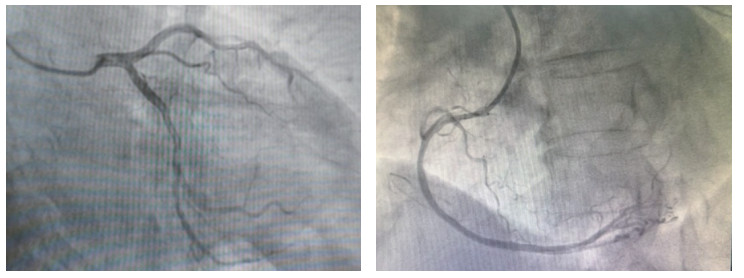

入院后按照急性冠脉综合征的流程诊疗,12:20紧急行冠状动脉造影,结果显示(图 3)左主干、前降支、回旋支及右冠状动脉血管通畅,TIMI 3级血流,未见明确狭窄或血栓形成,未行介入治疗。术中患者再次发生pVT,予以电除颤3次,并静脉注射胺碘酮(150 mg,15 min内静推)与艾司洛尔(10 mg,缓慢静推)控制心律。患者入住病房后仍反复出现恶性心律失常:13:10、13:15先后发生pVT,各予200J同步电复律;13:21出现心室颤动(ventricular fibrillation, VF),电除颤5次,并予利多卡因100 mg静推。后续予艾司洛尔、胺碘酮、利多卡因持续静脉维持,甲泼尼龙500 mg/d冲击,奥美拉唑抑酸,辅酶Q10及极化液等支持治疗。

| 图 3 冠脉造影结果显示左主干、前降支、回旋支及右冠状动脉血管通畅,未见明显狭窄或血栓形成 |